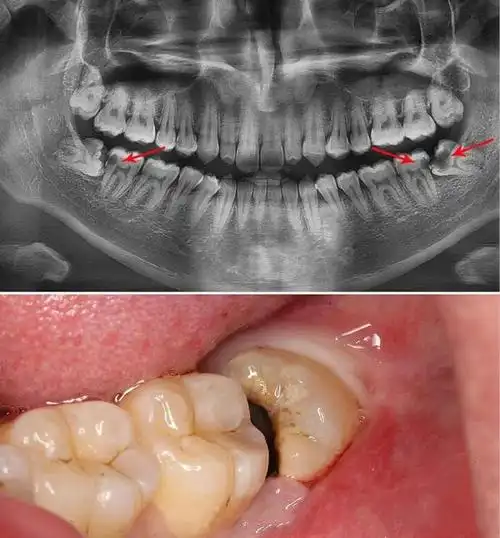

为什么智齿总是横着长

什么样的智齿需要拔来来来教你一分钟自检智齿隐患